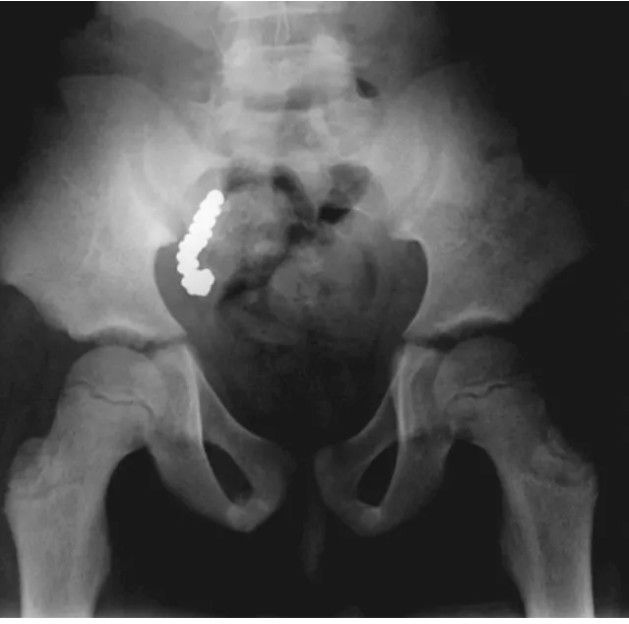

An 8-year-old boy in Australia had high levels of lead in his blood for more than two years for unexplained reasons, until doctors found lead pellets in his body, trapped in an unlikely place, according to a report of his case published in Aug. 8 issue of the New England Journal of Medicine. When the boy developed a stomachache and was admitted to the hospital, the doctors did an x-ray, which revealed a large number of small round objects in the boy's abdomen, appearing to be inside the digestive tract. The doctors immediately gave the boy a bowel washout, which should have cleared any object within his digestive tract, but a second x-ray showed the objects had not moved. The doctors suspected the unlikely scenario – the objects had to be lodged in the boy's appendix. In surgery, the doctors removed the boy’s appendix, and found it weighed five times heavier than normal. When they cut it open, they found 57 lead pellets trapped inside. It turned out, the boy’s family had hunted for food with a gun that fired such pellets, and the boy had consumed them while playing a game with his siblings. By: https://www.livescience.com/37919-oddest-medical-case-reports/3.html